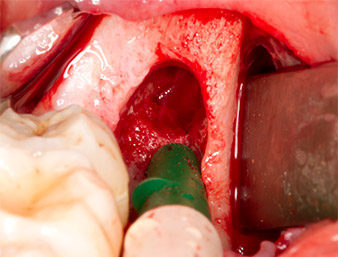

Tessuto di granulazione

Fig. 4: Due retrattori Langenbeck e una curette espongono l'area dell'intervento. È visibile il tessuto di granulazione della prima osteotomia non completamente cicatrizzata.

Il tessuto al di sopra del residuo di radice non era completamente ossificato ed era costituito per la maggior parte da tessuto di granulazione modificato dall'infiammazione (Fig. 4).

Dopo l'anestesia tronculare e l'anestesia locale, il sito operatorio è stato aperto e il tessuto molle esposto per l'accesso retromolare boccale (Fig. 3).